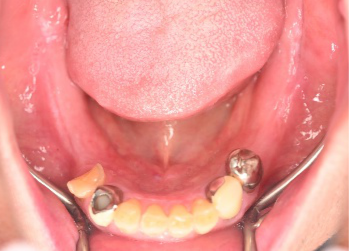

男性 Kさん 60代 (インプラント)

主訴

下の左右歯がないところに歯を入れたい。

治療内容

左右それぞれ3本歯がないところに2本ずつインプラントを埋入しました。

所感

上と下の歯の咬合接触がないすれ違い咬合です。上下義歯で対応するには最も難しいタイプの欠損状況です。治療開始前は、上下部分入れ歯が入っていましたが、入れ歯の安定が悪く、あちこちの歯茎に入れ歯が当たって痛く、満足に噛める状態ではありませんでした。上顎は、残ってる歯を活用するマグネット式総義歯を、下顎はインプラントを提案しました。上顎は、現在残っている歯の根管治療中です。上顎にマグネット式総義歯がはいれば、何でも食べられるようになります。

インプラント4本:¥363,000×4本=¥1,452,000(税込)

ポンティック2本:¥115,500×2本=¥231,000(税込)

合計:¥1,683,000(税込)

Before

▼初診時に使用していた部分入れ歯を装着したところ

▼インプラント埋入前

After

▼インプラント埋入後